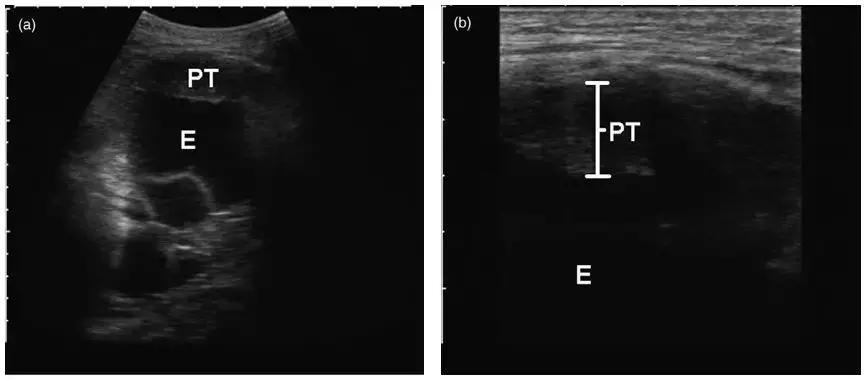

这是在彩超引导下的胸膜活检,胸水较少,胸膜局灶增厚。在穿刺中,可以看到针的所在位置。

优点:实时引导、无射线暴露、费用相对较低。

缺点:依赖超声仪器品质,因为不同的机器达到的效果不同;另外,由于超声扫描的Total的放置角度、位置都对成像有影响,所以超声医师的经验也很重要。